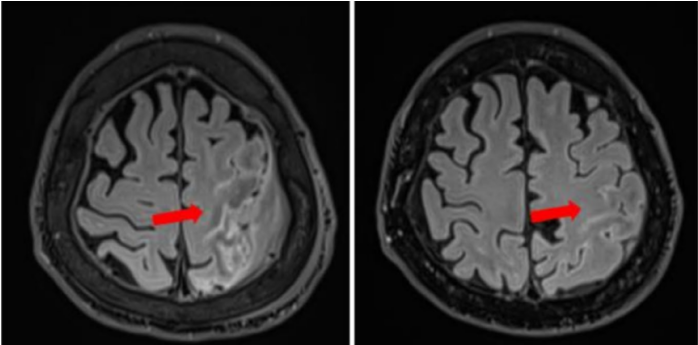

图2 | 患者2接受匹妥布替尼治疗的影像学表现:MRI在基线期(左图)及治疗3个月时(右图)的对比

72岁确诊BNS,出现语言障碍,MRI显示双侧额叶白质T2-FLAIR高信号增强,左额叶皮质增厚伴对比增强,对侧类似异常改变复发。

患者进行伊布替尼治疗60个月后进展,表现为语言障碍。

患者接受匹妥布替尼200mg治疗2周后语言功能改善,三个月时复查脑部MRI显示脑膜及邻近皮层区域的病理性对比强化范围缩小超过50%,左额叶仅残留最小程度脑膜增强。影像学检查同时显示T2-FLAIR高信号范围显著缩小,但已伴有早期组织萎缩征象。

患者接受匹妥布替尼治疗5个月(持续中);血液学反应PR,临床反应PR,影像学反应PR。